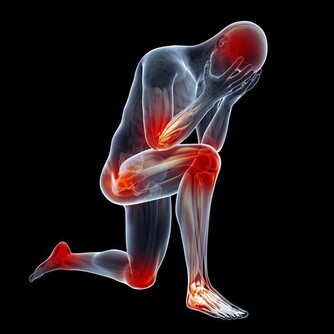

1.解熱、陣痛:青椒屬於辛溫,可以透過讓身體發汗而降低體溫,同時緩解肌肉疼痛。